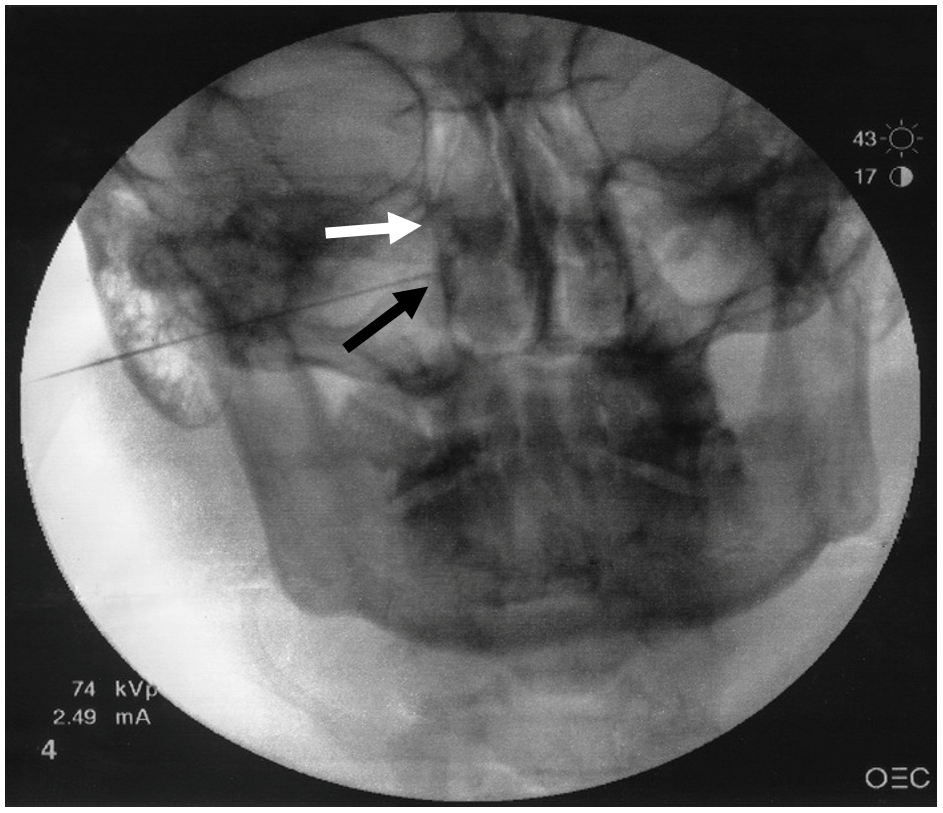

- An anteroposterior (AP) view is intermittently obtained to check the depth of the needle and avoid any breach to the nasal wall. The needle tip should terminate immediately lateral to the ipsilateral nasal wall as shown in the anteroposterior (AP view) (Figure 2).

Figure 2. Anteroposterior fluoroscopic view.

White arrow represents lateral nasal wall. Black arrow represents needle tip lateral to ipsilateral nasal wall.